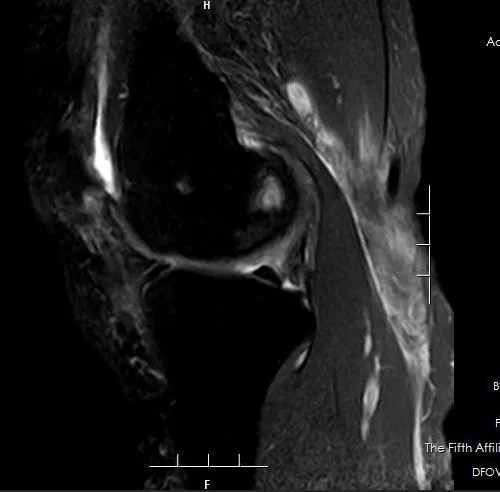

▲ 术前MRI检查巨大囊肿

▲ 术后复查MRI囊肿明显缩小,随着囊壁的闭合,囊肿会逐渐消失